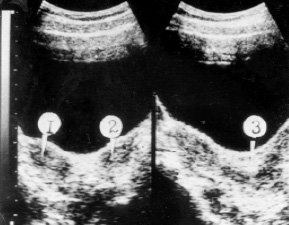

Обследовано 38 девочек с частичной аплазией влагалища (рис. 4) в возрасте от 11 до 19 лет (средний возраст 14,3±0,2). При обследовании у 7 девушек выявлены аномалии других органов и систем: у 2 - аплазия левой почки; по 1 - удвоение чашечно-лоханочной системы, дисплазия тазобедренного сустава, синдактилия, косоглазие, недоразвитие верхней челюсти, тугоухость.

Рис. 4. Частичная аплазия влагалища при функционирующей матке.

1 - матка (гематометра); 2 - гематокольпос; 3 - мочевой пузырь.